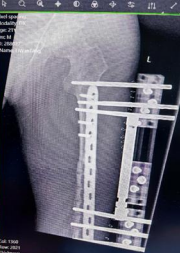

Ilizarov骨延长手术中医师需要在左股骨截骨延长单边轨道外安装一个固定支架,就像盖房子的脚手架一样,通过钢针将外固定架和病损骨骼连为一体,医生会在骨骼上做适当的截骨,再慢慢延长使骨骼延伸生长。

经过周密的术前准备,李先生被推进了手术间,在医院麻醉团队的密切配合下,经过数小时的精细操作,唐继全成功为患者施行了左股骨截骨延长单边轨道外固定支架固定术。

唐继全介绍,Ilizarov骨延长技术是在适当的牵张应力刺激下,使骨组织和周围其他软组织加速增长,总长度甚至可以达到10cm以上,该技术已被广泛应用到多种复杂病例的治疗中,包括但不限于骨关节畸形矫正、骨缺损修复、肢体不等长调整以及骨髓炎等顽疾的根治,在以上治疗中均展现了令人震撼的神奇疗效,因此被称为神奇的“魔架”。